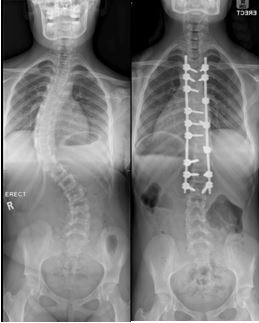

Adolescent idiopathic scoliosis is the most commonly found type of scoliosis in children. As the name implies, this is usually identified with the advent of the teenage growth spurt. The risk in these cases, beyond the general quality of life, is excessive deformity, resulting in effort intollerance, again through chest wall deformity.  Unacceptable cosmesis can also cause severe emotional distress in the teenage patient.  As this usually presents during adolescence, the spine can be considered to have grown enough to be considered as “grown”. As there is no further growing required, a definitive fusion procedure can be performed when indicated, fixating the spine in a more favourable position, a permanent solution. “I can attest to the dramatic personality transformation and change in confidence, in teenagers having to deal with a perceived malformed body, turning into confident and happy young people, through an appropriate intervention at the right time. A real metamorphosis with transformation into a butterfly,” says Dr Davis.

In adult patients, scoliosis is encountered for various reasons, sometimes through degeneration, or progression of a mild adolescent idiopathic scoliosis curve through degenerative “age-related” changes in the spine. Unfortunately, in some cases, adult spinal deformity is brought on by failed previous spinal procedures resulting in loss of hollow-curve of the lower back. Once the tall spinal column is pushed out af acceptable alignment one has to utilise compensatory trunk- and lower limb muscles and methods to allow erect stance. For patients, this in turn causes rapid fatigue due to inefficient energy consumption, a diminished walking distance and pain, often with severe debility.

These are potentially very difficult patients to deal with due to other existing co-morbidities such as osteoporosis, diabetes, heart conditions or other illness often part and parcel to patients in this age group.

The surgery requires break-down of prevoius fusions done in a poor position, and in severe cases, bony wedges can be cut out of the spinal column to re-attach and fix the spine in a more appropriate and well aligned position, to establish a normal stance and walking abilities.

This type of re-constructive surgery is difficult and only suited to a select group of patients that can safely endure such an extreme intervention.